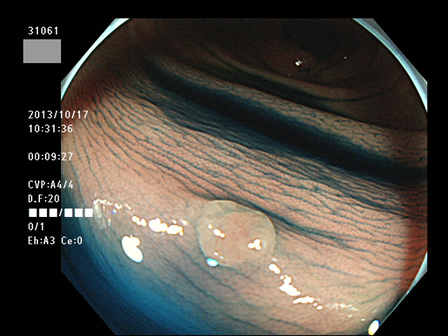

上記100名より抽出した平坦・陥凹型腺腫(=癌化の危険が高いが見落としやすい病変)の内視鏡写真